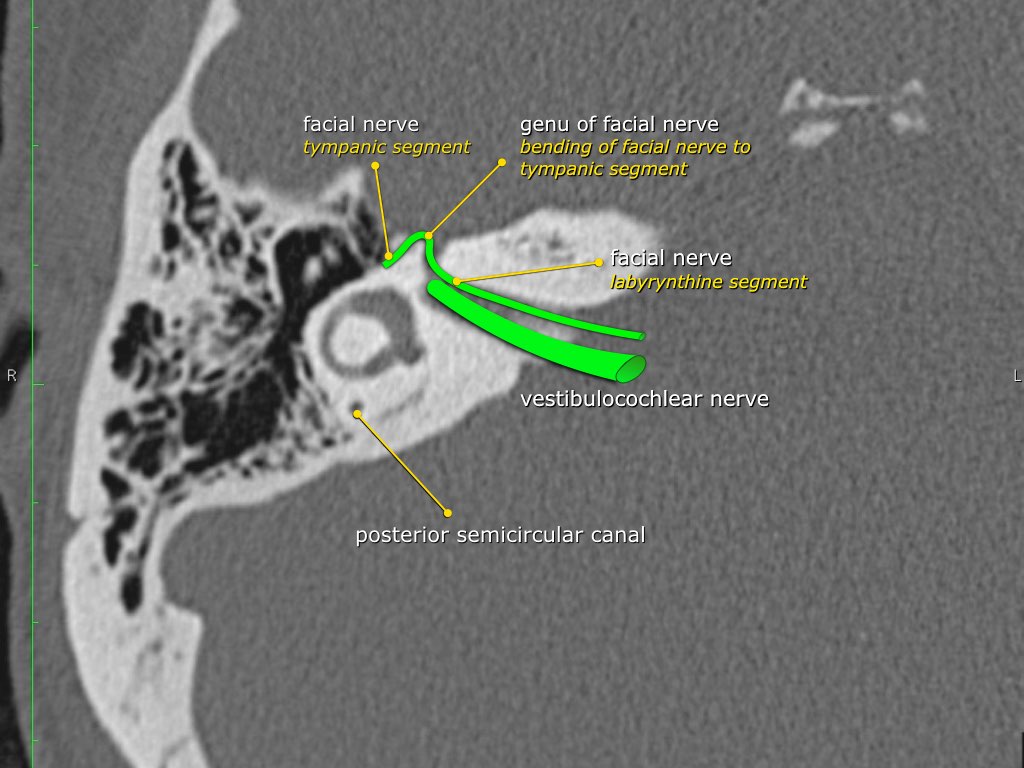

Đoạn mê nhĩ của dây thần kinh mặt xuất phát từ ống tai trong, chạy gần như vuông góc với trục dài của xương đá, gập góc nhọn về phía trước để đến hạch gối (geniculate ganglion).

Tại hạch gối, dây thần kinh mặt tạo thành một khúc quặt hình chữ U (genu thứ nhất của dây thần kinh mặt) để chạy ra phía sau theo đoạn nhĩ dọc theo thành trong của thượng nhĩ.